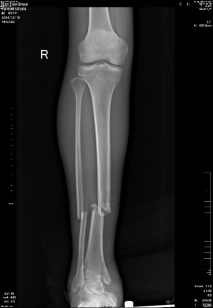

患者,男,22歲,車禍致右小腿疼痛腫脹,經(jīng)X片檢查提示:右脛腓骨折骨折。